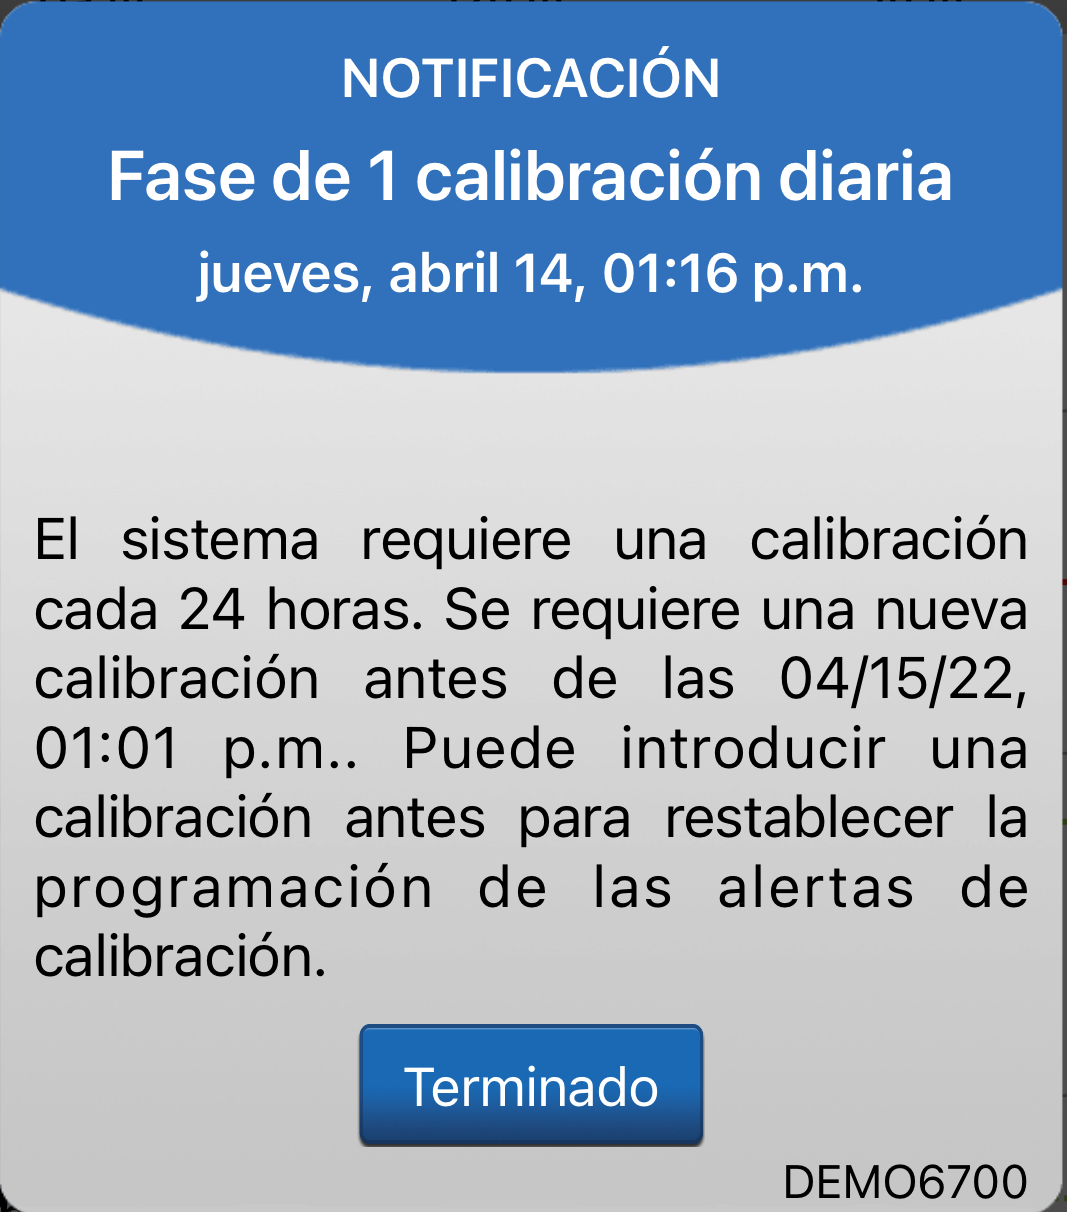

Aquí mostramos cómo funcionan juntas las alertas y notificaciones de calibración.

Cuando reciba la alerta Calibrar ahora y responda introduciendo

el valor de glucosa en sangre mediante punción capilar, recibirá una de estas dos notificaciones

si hay una actualización en

el momento de la próxima calibración.

ALERTAS Y NOTIFICACIONES DE CALIBRACIÓN

Si aparece la notificación Fase

de 1 calibración diaria, significa que solo se necesita una calibración al día. Por tanto, verá las alertas "Calibrar ahora" cada 24 horas.

ALERTAS Y NOTIFICACIONES DE CALIBRACIÓN

Cuando introduzca dicha calibración durante la fase de 1 calibración diaria, su siguiente calibración obligatoria se deberá efectuar en 24 horas.

En la fase de 2 calibraciones diarias, su siguiente calibración obligatoria se deberá efectuar en 12 horas.